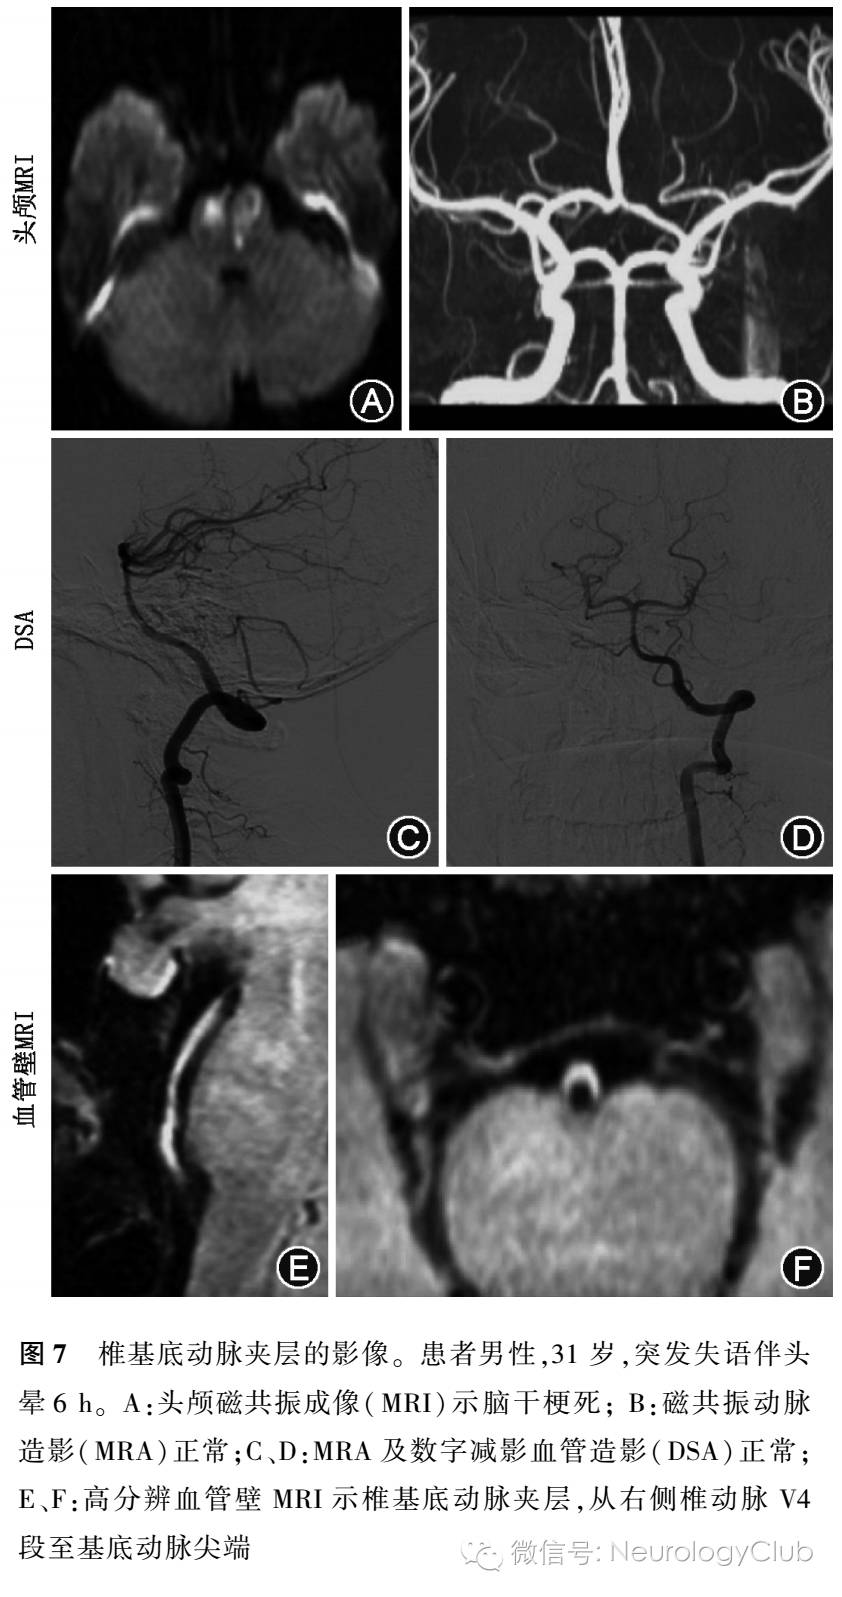

近年已应用于临床的3.0T HRMRI乃新型的血管成像技术,不仅可以进行管腔成像,而且能够直观显示管壁结构。高分辨率血管壁MR成像检查主要包括2D和3D序列两大类,2D序列即常规的黑血T1WI加权成像;3D序列包括:亮血的TOF-MRA、黑血的磁化准备快速梯度回波序列(magnetization prepared rapid acquisition gradient echo)、采用反转恢复和多回波来评估出血的扰相梯度回波脉冲序列(spoiled gradient recalled echo pulse sequence for hemorrhage assessment using inversion recovery and multiple echoes)、各项同性容积采集快速自旋回波(volumetric isotropic TSE acquisition)、三维运动敏感驱动快速梯度回波(3D motion-sensitizing driven equilibrium rapid gradient echo sequence)、非对比血管成像与斑块内出血同时成像(simultaneous noncontrast angiography and intraplaque hemorrhage,SNAP)等。

上述序列在相同的扫描时间下,2D和3D序列具有相似的信噪比及形态学测量(如管腔面积、管壁面积及厚度等),但也有着各自的优缺点。其中SNAP序列可以同时管腔和管壁成像,通过1次采集同时观察动脉粥样硬化的2个相关信息,即管腔狭窄情况及斑块内出血信息,是近年来出现的最新成像序列,主要用来观察血管壁斑块内出血,可通过提高动脉斑块出血、管壁及管腔的对比,以及增加血流抑制的效果,提高出血的检出率。在测量管腔大小方面,SNAP与3D-TOF具有很好的相关性,SNAP的空间分辨率近似于对比增强MRA技术,可以达到0.5mm3,同时对流动伪影敏感度较低,避免了慢血流带来的饱和效应。SNAP是观察颅内外血管壁斑块出血和管腔的首选序列。

HRMRI目前已成熟应用于颅外颈动脉,可以准确评估颈动脉狭窄程度、血管夹层(图7)、动脉斑块的诊断。3.0T的黑血HRMRI能够客观地显示多种类型的颈动脉系统斑块,对颈动脉系统斑块进行定量分析,从而达到评估黑血MRA的临床价值以及预防颈部斑块的形成。然而,黑血MRA在检测斑块时是有缺点的,如较长的扫描时间、无法重建图像、在异常部位对血管的检测范围受限。再者,黑血MRA在临床实践的功效也是有限的。因此,亮血与黑血MRA的联合使用被认为是鉴别脑血管斑块、血管腔狭窄、动脉粥样硬化斑块类型、斑块风险最有效的检查方法。这种组合检查方法为临床早期阶段的颈动脉系统斑块的治疗提供了可靠的方法。

MRI与MRA的联合使用不仅能提高诊断率,而且作为颈动脉夹层的非侵袭性检查,能够监测血管壁内血肿或并发症的进展与缓解。由于健康人的椎动脉直径偏小且多有变异,以至于MRI与MRA诊断椎动脉夹层的敏感度与特异度较低。CE-MRA可以显示血管腔的不规则,血管直径或血管阻塞的变化,以及假性动脉瘤的形成(图4)。CE-MRA在空间和时间上的分辨力不如传统的影像学检查,但具有非侵袭性检查的特点。CE-MRA具有它的优势,它可以补充T1加权、T2加权轴向图像,通过管腔狭窄段进一步明确动脉夹层,显示相关受损的脑组织,监测血管再通、血管阻塞的进程,对患者的后期管理提供更充分的依据。